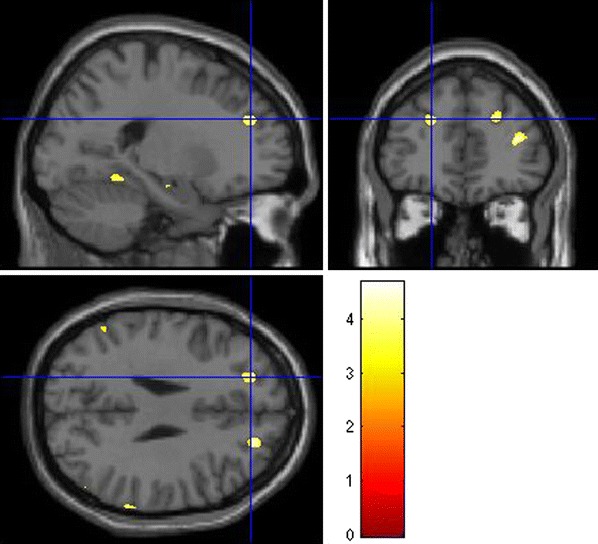

We found significant effects of the DTNBP1 SNP rs2619522 on grey matter brain volumes. The major finding was in the left hippocampus with significantly altered grey matter volume associated with the risk allele (G allele; Fig. 1). This result remained significant after false discovery rate (FDR)-correction (p FDR-corr = 0.042) and only scarcely missed the significance level for family wise error (FWE)-correction (p FWE-corr = 0.069).

Fig. 1.

Effects of DTNBP1 SNP rs2619522 on hippocampal grey matter volumes. Carriers of the G allele (risk allele) show significantly higher grey matter volumes in these brain regions than T/T homozygotes. p < 0.001 (uncorrected); extent threshold = 100 voxels

In addition, we found significant effects on a FDR-corrected level contralateral in the right hippocampus (Fig. 1) as well as in anterior prefrontal (Fig. 2) and intraparietal cortices (Fig. 3), in cortical regions of the temporal lobe and bilaterally in the cerebellum.